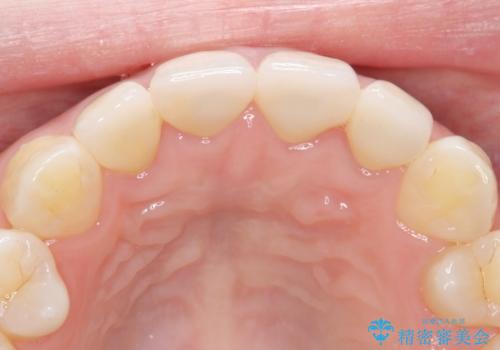

【精密根管治療+オールセラミッククラウン】より自然な前歯にしたい!

- 他院で治療した前歯が白すぎること、時々ズーンと痛むことを主訴に来院されました。

根っこの先端に病気も見つかったため、根管治療からやりかえて治療を行なっています。

被せ物の製作時は、患者さんと技工士さんが直接話をすることで、より満足度の高い治療を行うことができました。